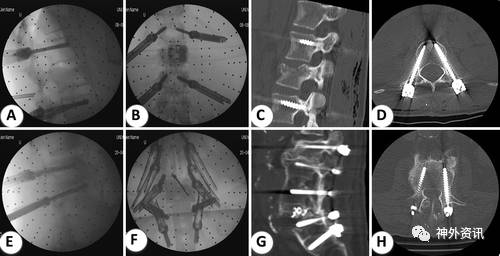

通过术后CT扫描评估1857个螺钉的位置,其中1799个(96.9%)为可接受的或良好的结果,38个螺钉(2%)显示3-6mm的位置偏差,20个螺钉(1.1%)的位置偏差>6mm(图1)。7例患者的9个错位螺钉进行重置手术。406例患者的螺钉总重置率为1.7%。患者平均住院时间为13.7±9.1天。27例(6.7%)患者发生伤口愈合问题,其中20例(4.9%)需要进行修复手术。26例(6.4%)患者硬脊膜撕裂,而且均在减压骨置入术中,其中2例(0.49%)术后CSF漏和伤口愈合差进行再次手术。4例(0.98%)患者出现新的神经功能缺损。术中持续辐射暴露时间平均114.4秒±72.5秒(表2)。

图1. 1例L-4骨折的年轻患者在术中X线透视图像(A和B)和术后CT扫描图像(C和D)显示螺钉放置良好。另1例肥胖患者的术中X线透视图像(E和F)和术后CT扫描图像(G和H)显示植入物因退行性脊椎前移而松动。